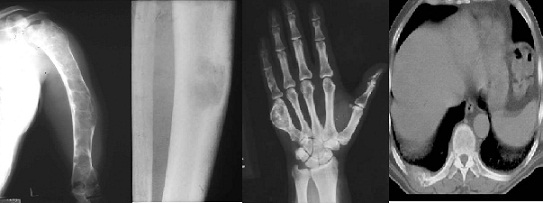

Рак Кости Фото

Рак Кости Фото 77 фото